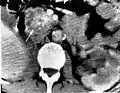

El cistoadenoma seroso del páncreas es un tumor benigno de este órgano. Generalmente se encuentra en la cola del páncreas,[1] y puede estar asociado con el síndrome de von Hippel-Lindau.[2]